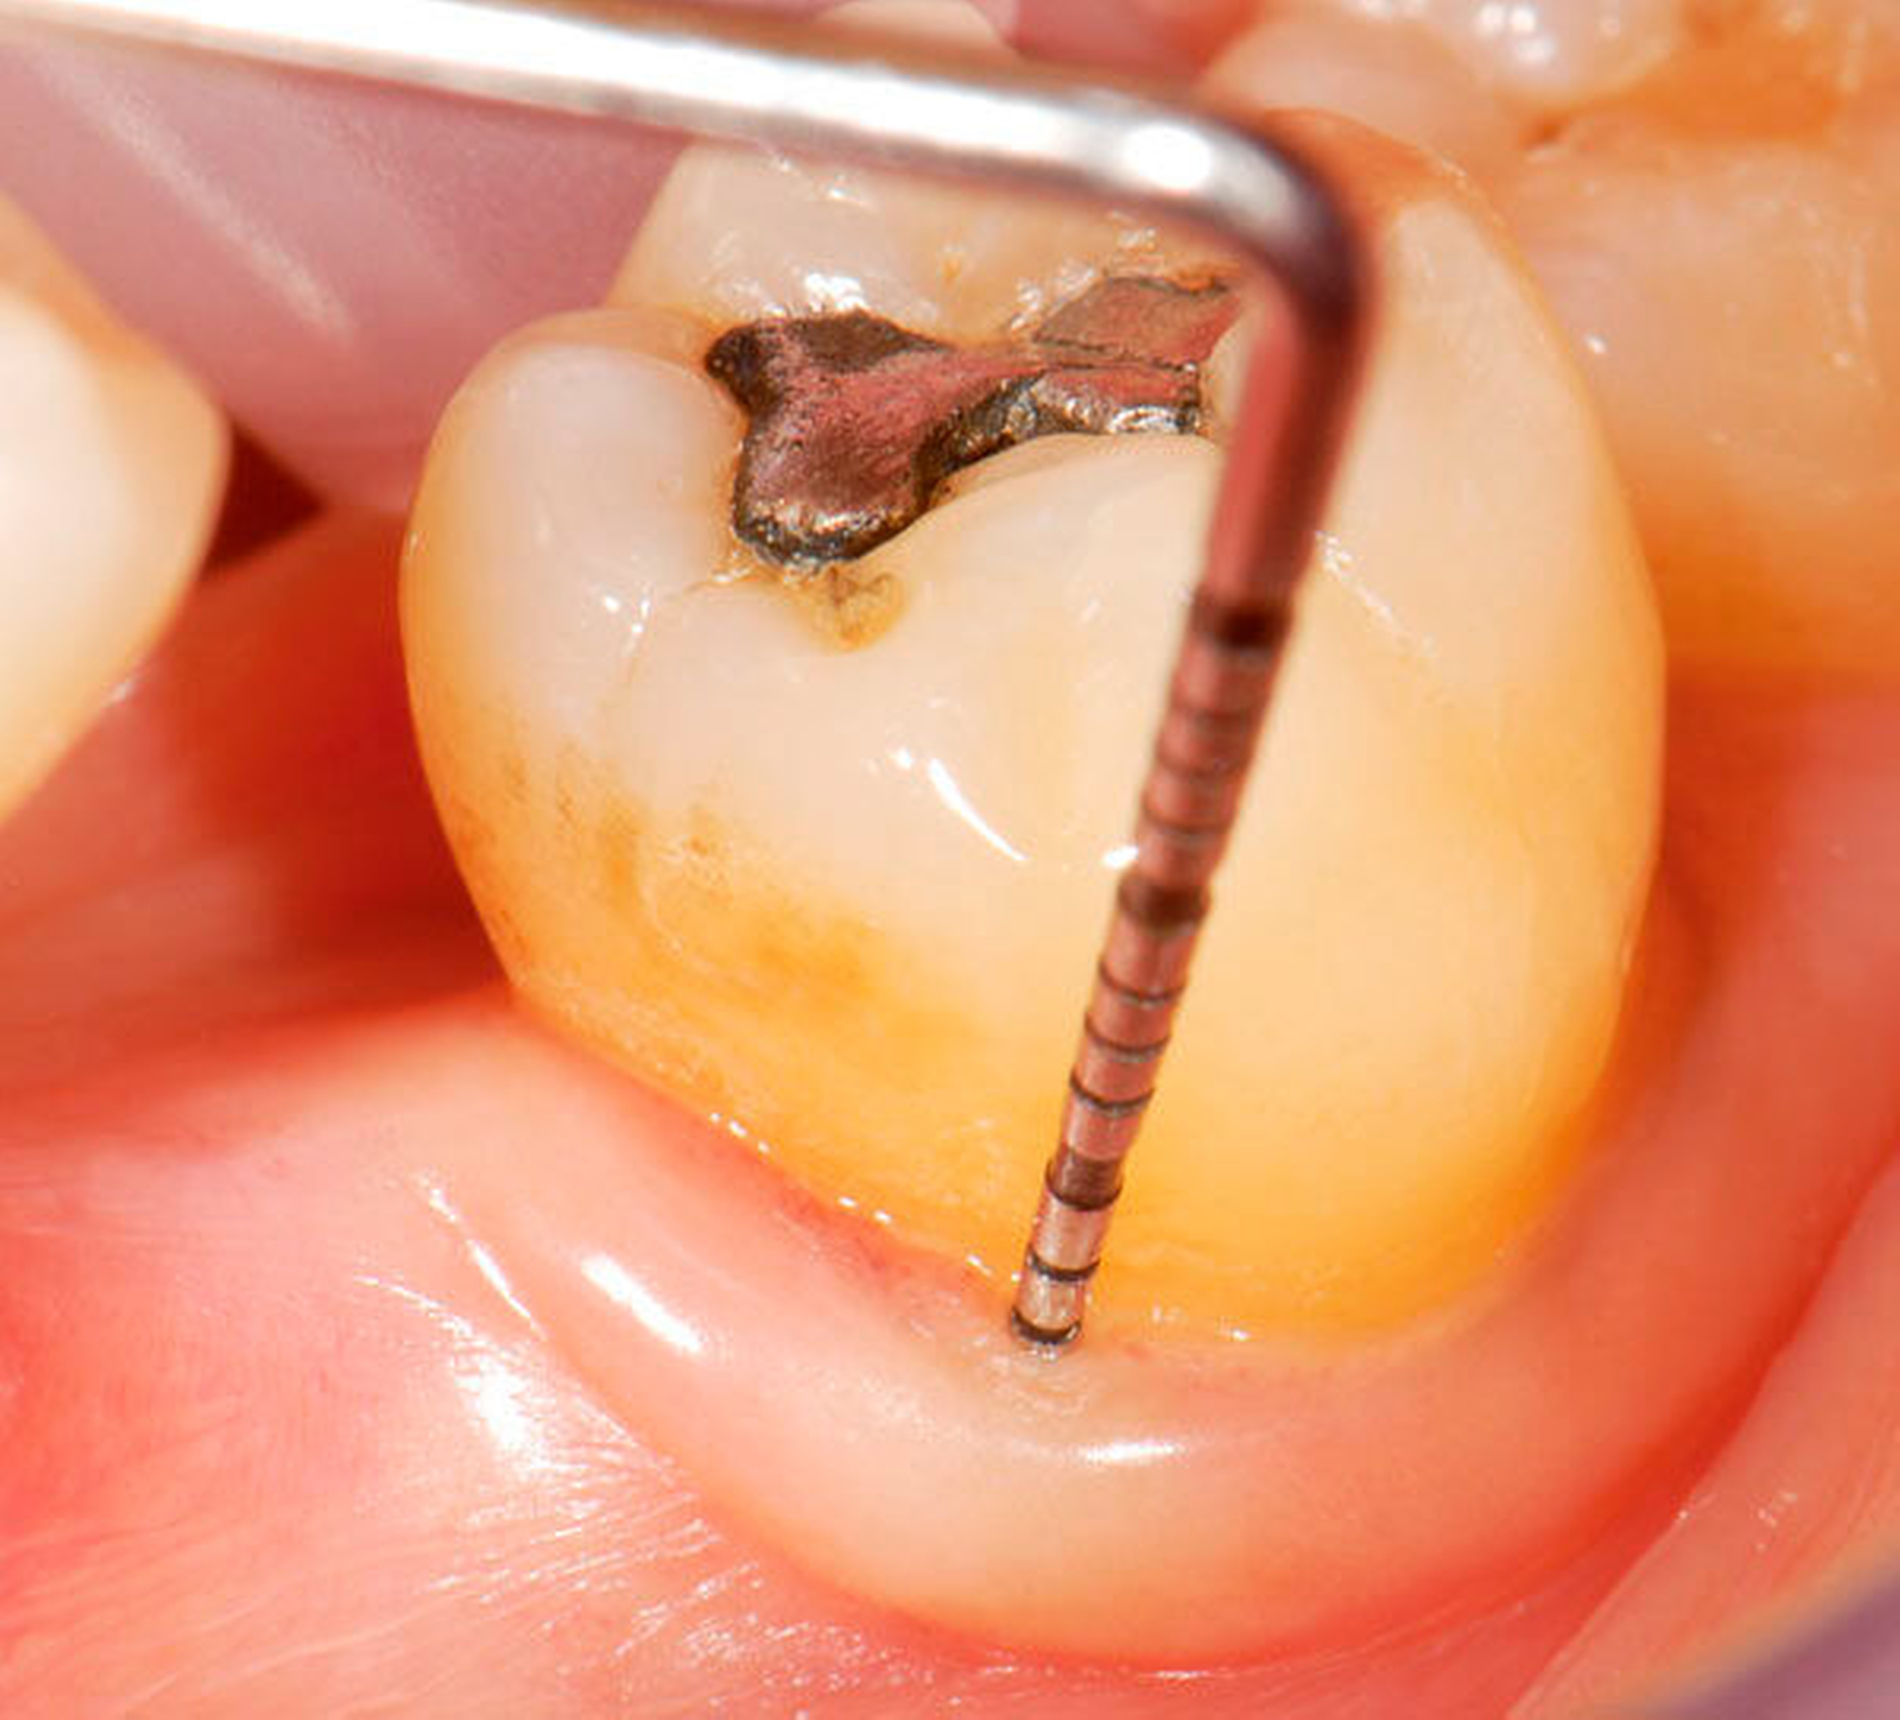

Abbildung 3: Direkte Reparatur im Seitenzahnbereich (R2-Technik)

In den Abbildungen 1 bis 3 werden Optionen für frugale Interventionen auf restaurativem Sektor aufgeführt. Es handelt sich um direkte Vollüberkronungen im Frontzahnbereich (hier: hergestellt in R1-Technik / einphasig) (Abbildung 1), direkte Teilüberkronungen im Seitenzahnbereich (hier: hergestellt in R1-Technik / einphasig) (Abbildung 2), Reparatur-Restaurationen im Seitenzahnbereich (hier: hergestellt in R2-Technik / zweiphasig) (Abbildung 3). Technische Einzelheiten zur Vorgehensweise und den Ergebnissen sind an anderer Stelle beschrieben (Literatur siehe oben).

schadensgerechte Reparaturtechniken (Abbildung 3),